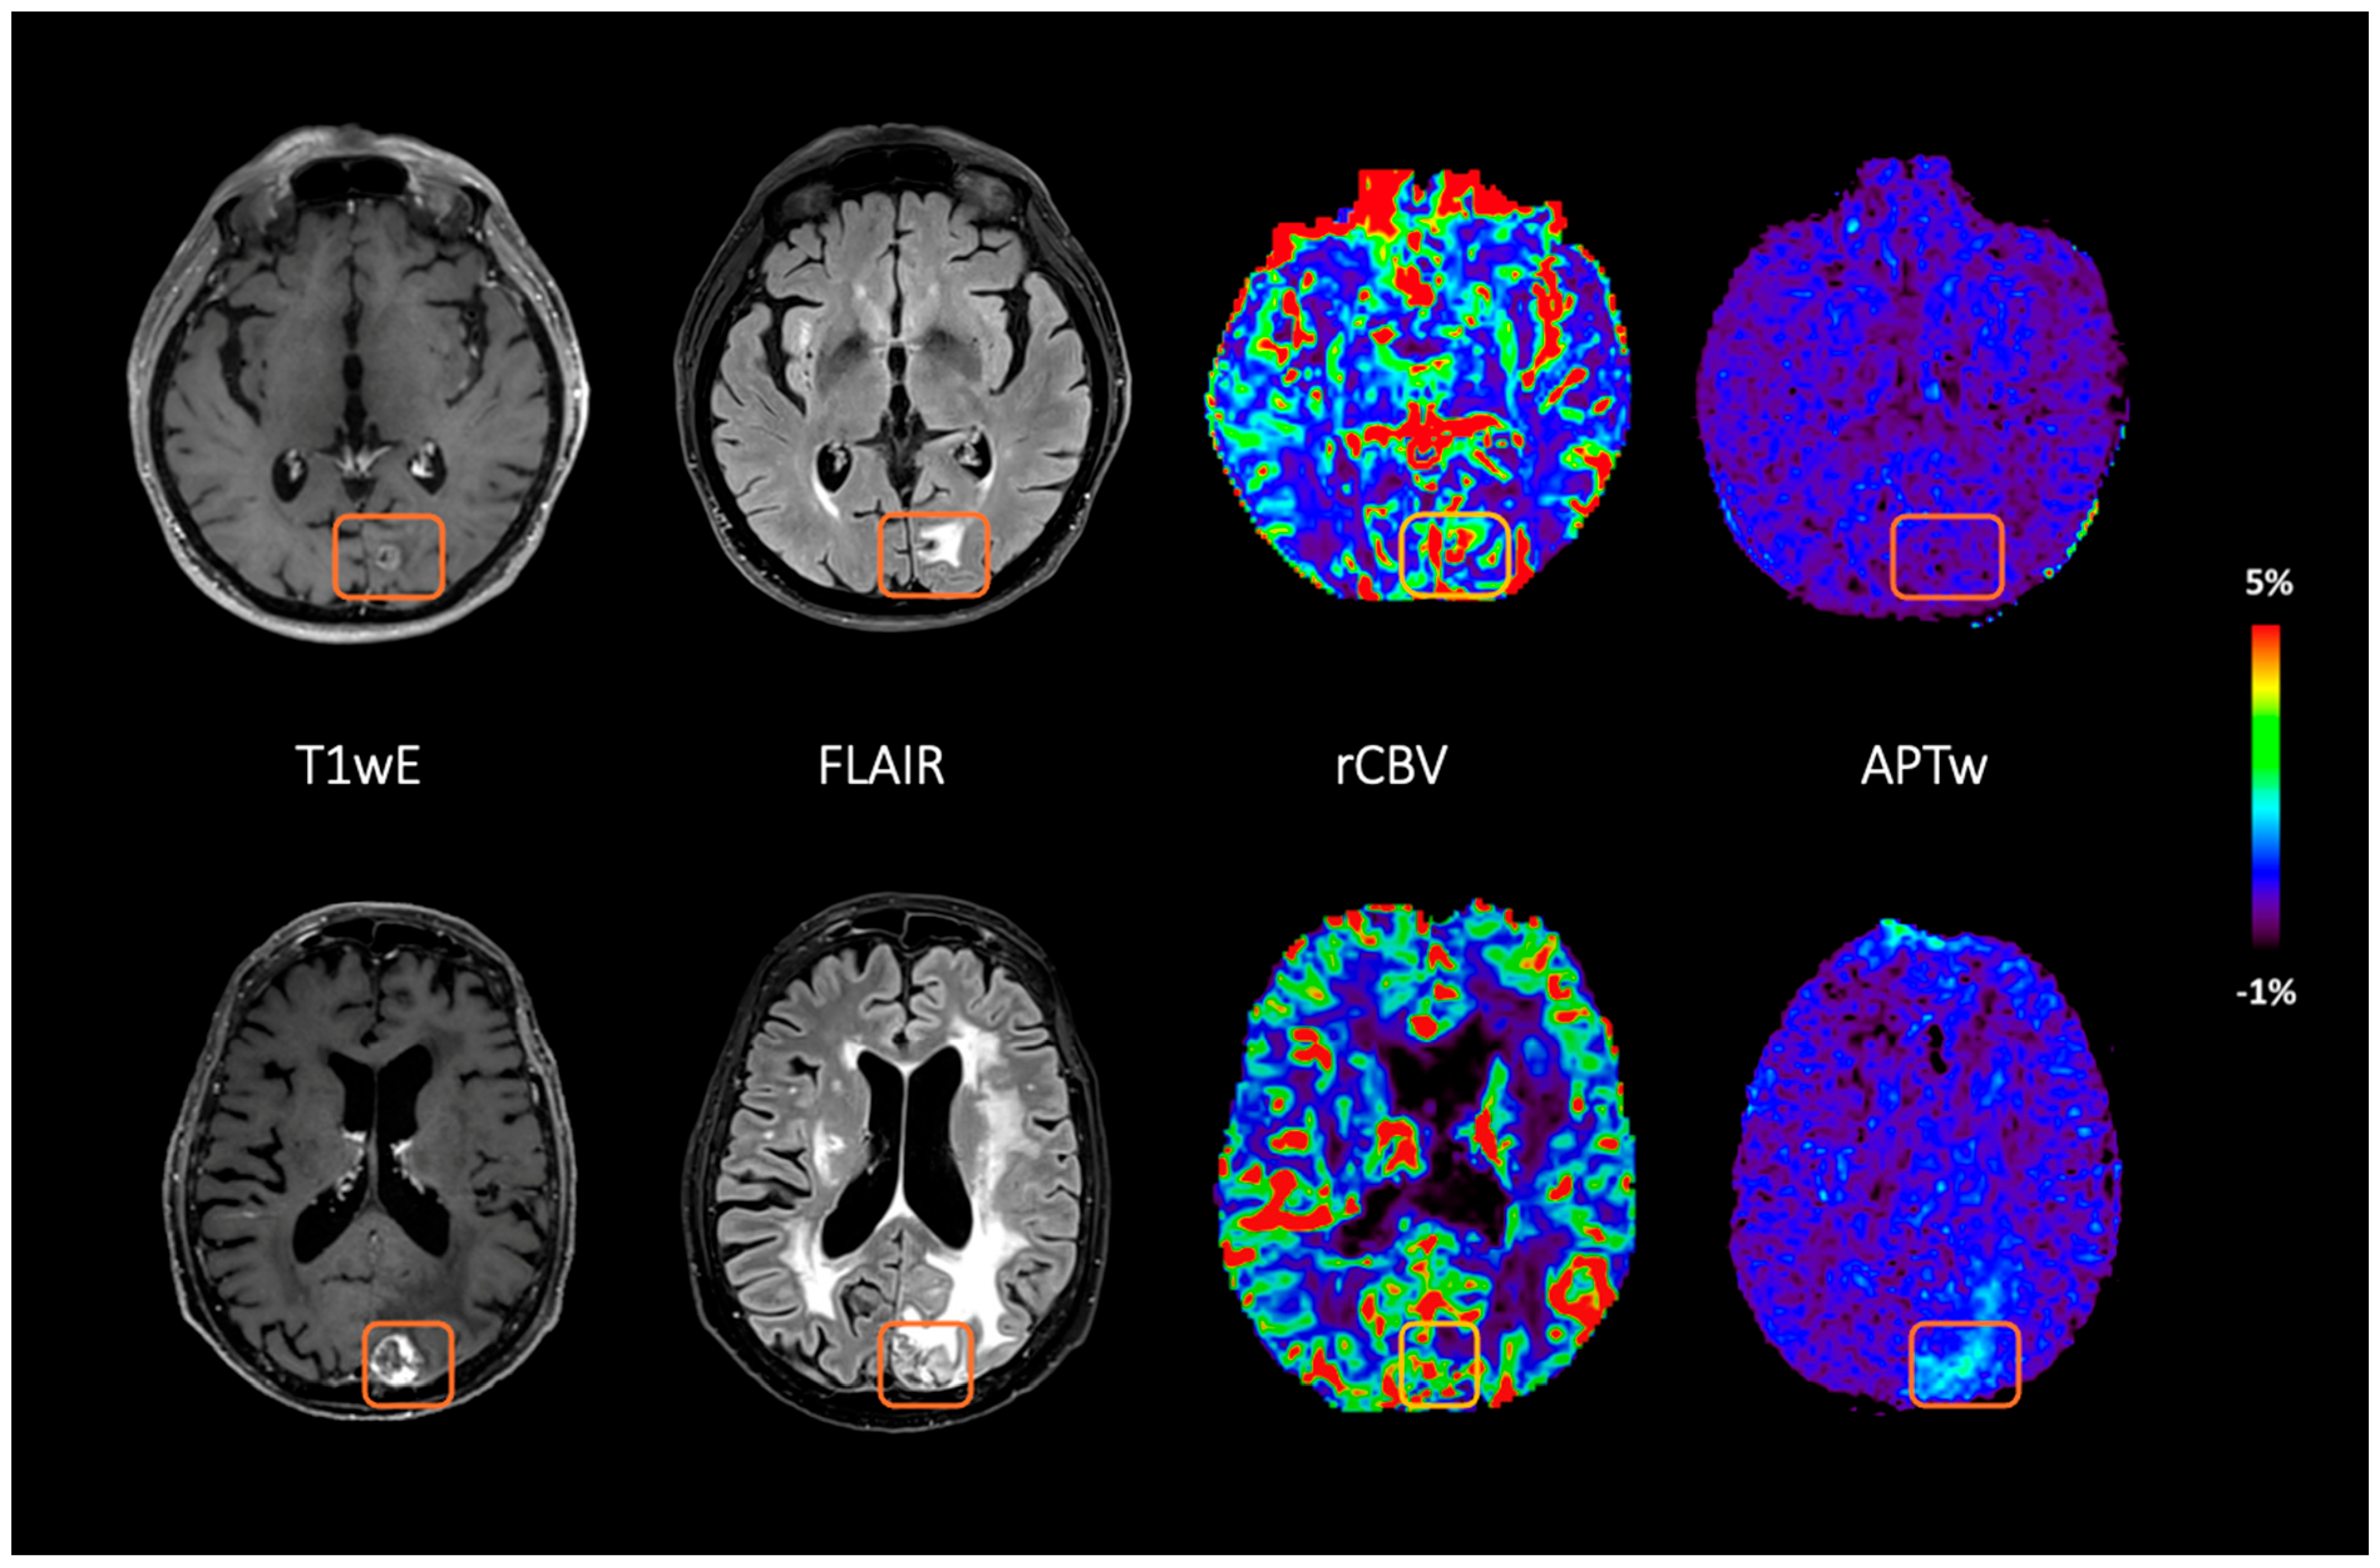

3.2. Ability of Fluid-Suppressed APTw and Leakage-Corrected rCBV to Distinguish Between RN and TP